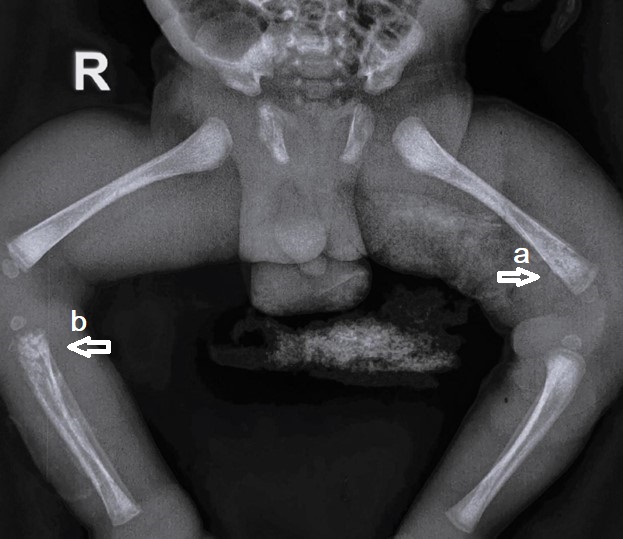

A 28-day old male neonate presented to emergency with a complaint of swelling left thigh for 7 days which increased over the last 3 days. There was a history of fever for 2 days and reddish discoloration of thigh skin for the last 2 days. The baby had decreased oral intake for 1 day. There was no history of trauma or massage. On examination, the baby was febrile with a heart rate of 138/min and had restricted movement of the left lower limb. Signs of inflammation were present. The baby was fluid resuscitated and routine sampling revealed Hb 12 gm/dL, total leucocytes count (TLC) of 17500/uL with neutrophils of 72 %, C-reactive proteins (CRP) were 332 mg/L and platelets of 1.6 lakhs/uL. Other blood parameters were normal except for high K levels (> 7 mmol/L). Supportive treatment was started for hyperkalemia and i.v. antibiotics [Cloxacillin, Amikacin as per hospital policy] started after sending blood cultures. X-ray left lower limb (LL) was done and revealed soft tissue edema and hypertrophy but no bony changes. The baby was kept on conservative management with i.v. antibiotics, limb elevation, and local hygroscopic measures to relieve tissue edema. Meanwhile, the baby developed swelling of the whole lower limb, though TLC and CRP were decreasing. In view of the deterioration of clinical condition, the baby planned for fasciotomy after 5 days and multiple fasciotomies of left LL were done [1 incision on thigh lateral aspect, incision each on medial and lateral calf, and 1 incision on dorsal foot]. It drained the intramuscular fluid and showed ischemic changes in the medial calf area but no pus was found. It led to clinical response in the calf area in the postoperative period. Blood culture revealed Methicillin-resistant Staphylococcus aureus (MRSA) and antibiotics were changed to vancomycin. The baby had improved in general condition. Thigh swelling had little response and the X-ray was repeated which showed periosteal elevation (Fig. 1). The baby underwent surgical drainage and around 50 ml of thick pus was drained. Pus culture also showed MRSA growth. The baby was discharged on oral linezolid after 1 week of i.v antibiotics. At 2 years and 7 months, the baby is asymptomatic and able to walk with support.

Figure 1

X-ray showing periosteal elevation of femur suggestive of subperiosteal collection.